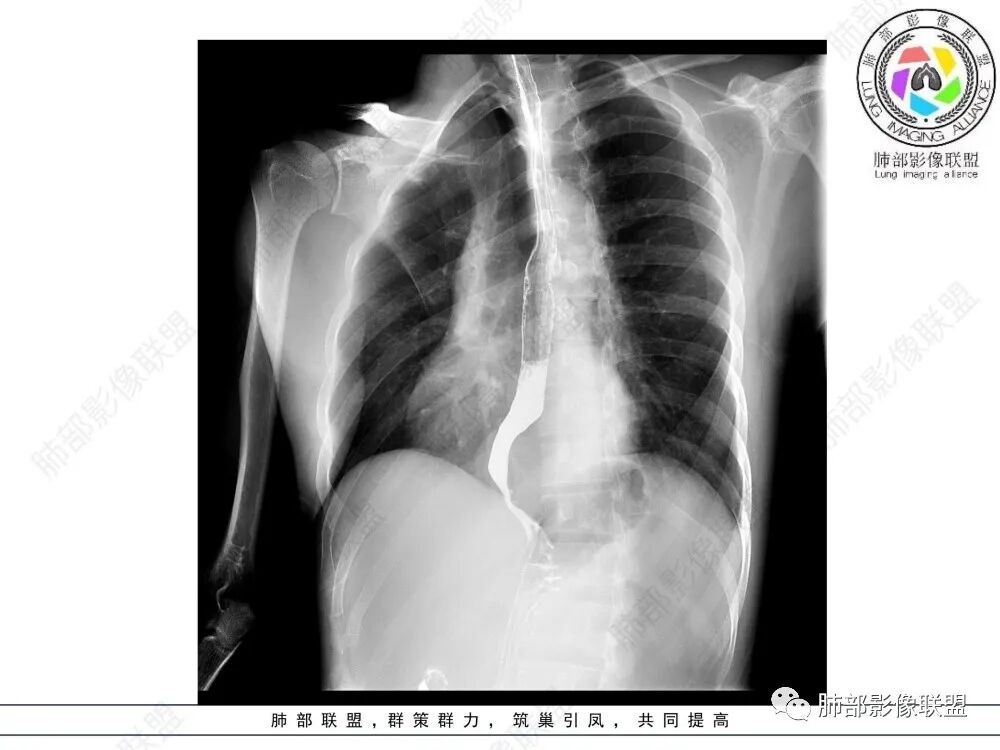

定位后纵膈,实性密度,增强轻度强化,T1等低信号T2低信号,弥散未受限。钡餐造影,食道及贲门管壁柔和,造影剂通过顺畅。考虑神经鞘瘤。鉴别食道平滑肌瘤。

食管下段肿块,环壁生长,分叶状,密度比较均匀,钡餐造影食管下段弧形受压移位,并可见龛影,考虑为食管平滑肌瘤或食管结核。

后面造影图,像腔外  南边老师看得仔细

造影虽然像外压,但是ct肯定更清楚,看ct就是一个环绕管壁生长,管腔狭窄,定位应该没有问题,但是大家病理都答对了,太厉害了

食管平滑肌瘤是最常见的食管良性肿瘤,多见于男性,男女之比为2.6:1,高发年龄 30~60岁之间与食管癌相比,食管平滑肌瘤 的一个主要特点是病史相对较长,病情进展缓慢。病史最长者达10年余,平均 15.7个月,尽管病史较长,但大多数患者仍能进普食。食管平滑肌瘤的诊断一般比较容易,结合患者临床症状、食管造影及食管镜所见,一般均能得出正确诊断。食管造影主要为充盈缺损,病变与食管壁成锐角,粘膜线连续无破坏,管腔收缩扩张比较自如。钡餐造影敏感性高,但对食管壁间及食管周围情况难以判断。CT具有极高的密度分辨率,并且可以获得高质量的多平面重组图像,有利于食管壁间及食管周围情况的判断,表现为食管下段环绕管壁生长,偏心性或薄厚不均软组织密度肿块,密度均匀,内缘分叶状,管腔与正常食管壁构成不规则多角形扩张,增强动脉期无强化,多角度重建其病灶长轴与食管长轴不一致。由于食管壁在收缩状态下厚度约为5.6mm,扩张状态厚度不超过3mm,CT扫描时保持食管处于扩张状态可提高小病灶检出率。MR表现为T1加权等信号,T2加权稍高信号,可见高信号粘膜层,增强扫描轻度渐进性强化,密度均匀,无出血坏死。对于粘膜及周围脂肪间隙的判断具有明显优势。